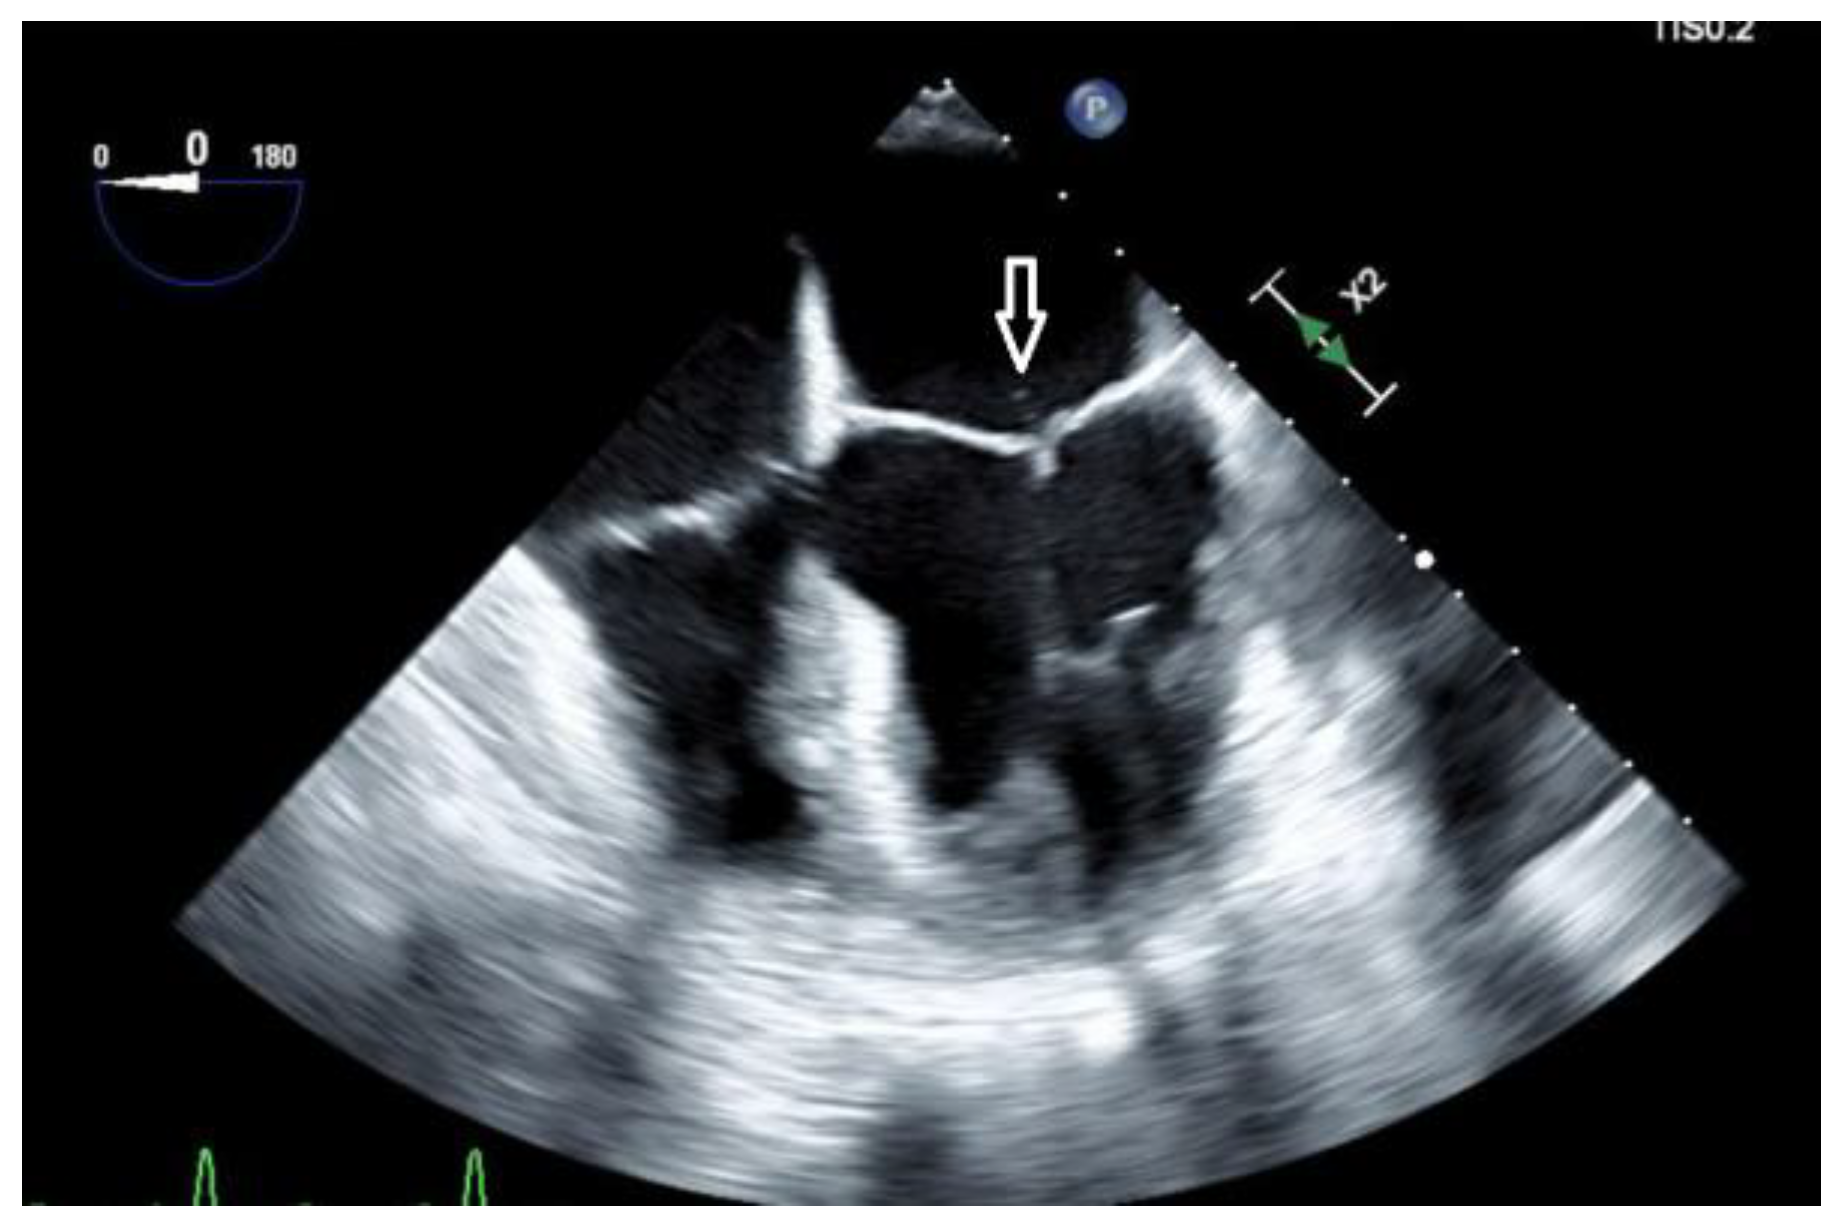

A trans-esophageal echocardiogram (TEE) showed a small mobile filamentous structure on the atrial side of the anterior mitral leaflet which was concerning for infective endocarditis (Figure 2).

Figure 2.

A transesophageal echocardiogram (TEE) showed a small mobile filamentous structure (white arrow) on the atrial side of the anterior mitral leaflet which was suggestive for infective endocarditis.